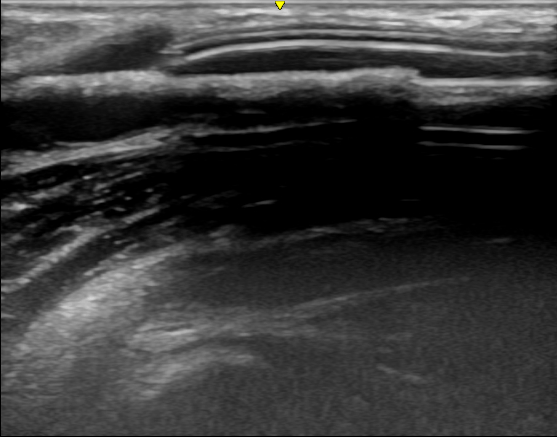

近日 , 西安交通大学第一附属医院肾脏内科透析通路团队为一位人工血管内瘘狭窄的患者成功实施了超声引导下覆膜支架植入术 , 这是陕西省首例在超声下进行的此类手术 , 标志着西安交大一附院透析通路介入治疗技术的又一次提升 。 患者为男性 , 55岁 , 诊断为慢性肾炎 , 慢性肾功能衰竭 , 使用左前臂人工血管内瘘规律透析1年 。 该患者此前因为人工血管内瘘狭窄曾接受两次经皮静脉球囊扩张术(PTA) , 但术后狭窄很快复发 , 对于这种狭窄容易复发且单纯PTA效果不佳的患者 , 覆膜支架植入术是比较好的解决方法 。 经过充分的术前准备和一个小时的手术 , 肾脏内科杨世峰副主任医师及其团队成功为该患者实施了超声引导下覆膜支架植入术 , 术后患者人工血管内瘘血流恢复通畅 , 透析过程中血流量充足、静脉压正常 , 达到了较好的手术效果 。

血液透析通路是尿毒症患者的“生命线” , 目前尿毒症患者最常用的透析通路是自体动静脉内瘘和人工血管内瘘 。 然而内瘘无法避免的并发症就是狭窄 , 长期高速的血流会引起血管内膜反应性增生 , 导致内瘘管腔狭窄和血流量不足 , 影响透析效果 , 狭窄严重时导致内瘘闭塞、血栓和失功 。 处理动静脉内瘘狭窄最有效的方法就是PTA , 通过血管腔内治疗的方法解除狭窄 , 具有创伤小、恢复快的优点 。 然而部分病例单纯PTA后狭窄容易短时间内复发 , 对于这些病例覆膜支架植入是较好的解决办法 。 传统的支架植入术是在DSA造影下进行 , 而超声引导下介入手术是近几年新兴的技术 , 超声引导具有方便、无辐射损伤 , 无造影剂损害、可显示闭塞病变等优点 , 特别适合动静脉内瘘等外周血管的介入治疗 。